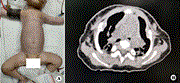

Bilateral correction of asphyxiating thoracic dystrophy

Wenlin Wang and others

Journal of Surgical Case Reports, Volume 2022, Issue 8, August 2022, rjac352, https://doi.org/10.1093/jscr/rjac352

Novel median thoracic expansion for asphyxiating thoracic dystrophy

Journal of Surgical Case Reports, Volume 2022, Issue 8, August 2022, rjac345, https://doi.org/10.1093/jscr/rjac345